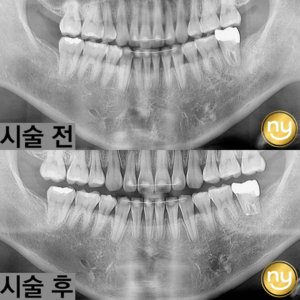

처음 본원에 내원하셔서 찍은 파노라마 사진입니다.

전체적으로 잇몸뼈의 소실이 심하고

하악의 브릿지와 크라운을 수복한 치아들도

염증이 발생되어 있는 것을 보실 수 있는데요.

염증과 치주 질환으로 인해 치아 흔들림이 심해 상악 송곳니 2개와

작은 어금니 1개를 제외하고는 살릴 수 있는 치아가 없어서

나머지 치아들은 발치를 진행하기로 했습니다.